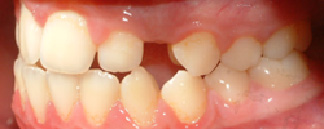

2) Οι φωτογραφίες του ασθενούς

Από τη μελέτη αυτών θα προκύψει εάν υπάρχει ορθοδοντικό πρόβλημα το οποίο μπορεί να εντοπίζεται μόνο στα δόντια ( συνωστισμός, στροφές, έκτοπη εντόπιση), είτε να υπάρχει και σκελετικό πρόβλημα ( στενή γνάθος, προγναθισμός ή οπισθογναθισμός, ασσυμετρίες, σκελετική υπερσύγκλειση ή ανοικτή δήξη).